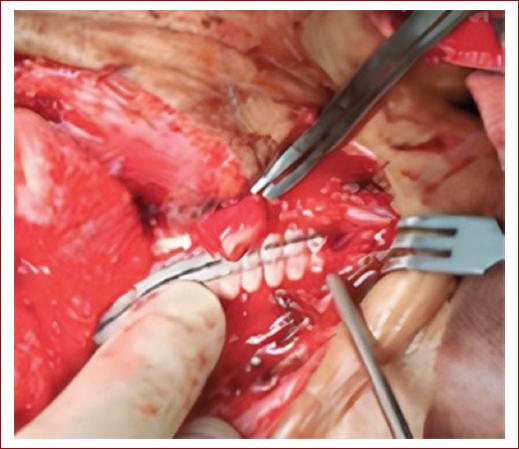

Se realiza abordaje subclavicular derecho extendido a región axilar, encontrando transección de arteria subclavia, vasoespasmo y trombosis de cabos, y laceración de vena subclavia. Se realiza control proximal y distal con clamps vascular en subclavia zona II y axilar, se dejó instalado tubo a tórax derecho, shunt intravascular temporal (TIVS) en arteria subclavia y venorrafia. Luego, se traslada a la paciente a unidad de cuidados intensivos y se reingresa a cirugía después de 21 horas para retiro de TIVS y bypass subclavio-axilar con un injerto de politetrafluoretileno (PTFE) de 6 mm (Fig. 2), una vez llevado a cabo el procedimiento y verificar hemostasis se realiza osteosíntesis de clavícula por parte del servicio de ortopedia.